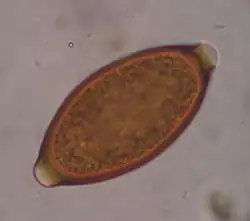

Trichuris trichiura, ou Trichocephalus trichiuris, est une espèce de nématodes (les nématodes sont un embranchement de vers non segmentés, recouverts d'une épaisse cuticule et menant une vie libre ou parasitaire). C'est l'un des parasites du tube digestif humain, dont des œufs fossilisés sont encore trouvés sur des lieux de fouilles archéologiques préhistoriques[1].

Ce parasite peut être mis en évidence par un examen parasitologique des selles chez le sujet infesté.